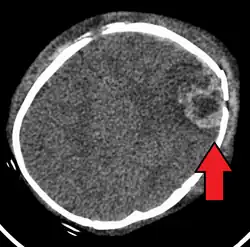

| An intraparenchymal bleed with overlying skull fracture from shaken baby syndrome | |

Diagnosis can be difficult as symptoms may be nonspecific.[1] Symptoms may include altered mental status, trouble breathing, and vomiting.[7] As a result, about 31% of true SBS cases may go unnoticed initially. However, imaging can provide valuable information about a potential SBS diagnosis.[58] Imaging must be performed within at least 24 hours of the suspected injury to detect brain edema characteristic of SBS.[59] A CT scan of the head is typically recommended if a concern is present.[1] If there are concerning findings, a brain MRI is also recommended, which can further reveal parenchymal injuries and hemorrhages.[58] It is unclear how useful subdural haematoma, retinal hemorrhages, and encephalopathy are alone at making the diagnosis.[11]

-

A skull fracture from abusive head trauma in an infant -

3D CT reconstruction showing a skull fracture in an infant -

3D CT reconstruction showing a skull fracture in an infant